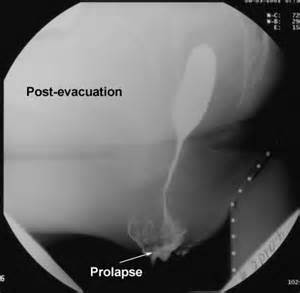

• Kontrastlı Rg-müayinə - “quş dimdiyi” əlaməti

Kontrastlı Rentgenqrafiya – “quş dimdiyi” əlaməti;